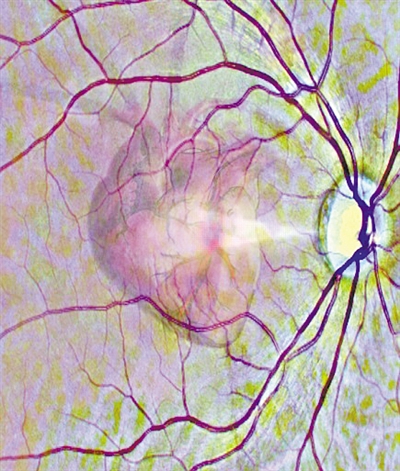

通过视网膜扫描来了解心脏健康状况(示意图)。图片来源:利兹大学官网MW4福鼎新闻网|今日福鼎|福鼎新闻信息权威发布平台

视网膜微小血管的变化是更广泛的血管疾病,包括心脏问题的指标。在英国利兹大学领导的这项研究中,研究人员利用深度学习技术训练AI系统自动读取视网膜扫描数据,并识别那些在接下来的一年中可能会得心脏病的人。深度学习是一系列复杂的算法,使计算机能够识别数据中的模式并作出预测。MW4福鼎新闻网|今日福鼎|福鼎新闻信息权威发布平台

一旦学习了图像模式,AI系统就可以仅通过视网膜扫描来估计左心室(心脏的四个腔室之一)的大小和泵送效率。心室扩大与心脏病风险增高有关。借助有关左心室估测大小及其泵送效率的信息以及有关患者年龄、性别等基本人口统计数据,AI系统可预测他们在接下来的12个月内心脏病发作的风险。MW4福鼎新闻网|今日福鼎|福鼎新闻信息权威发布平台